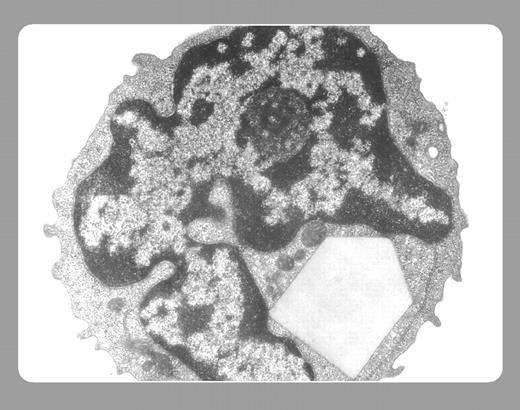

An electron micrograph reveals an intracytoplasmic immunoglobulin crystal, resembling baseball's home plate, in follicular small cleaved cell lymphoma. The immunoglobulin (Ig) crystal is within the endoplasmic reticulum. Ig crystals confined to neoplastic cells have been reported in 9 other cases of non-Hodgkin B-cell lymphomas of diverse histologic types.FIG1